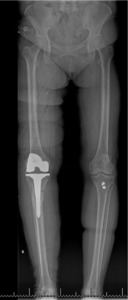

Pre-operative radiographs demonstrated Kellgren-Lawrence grade 4 tricompartmental osteoarthritis, 12° of tibial varus, a 22 mm deviation of the mechanical axis toward the medial side of the knee center, and an apex of angulation located 6 cm below the joint line (Figures 1 and 2). A follow-up computed tomography scan confirmed the absence of rotational malunion.

The total estimated blood loss was 300 mL, and no transfusion was required. The patient tolerated oral intake on the evening of surgery, completed her first physiotherapy session the following morning, and ambulated fifty feet with a rolling walker while wearing the hinged knee brace locked in extension. Following ambulation, full length lower extremity films were re-obtained, demonstrating neutral mechanical hip–knee–ankle axis (Figure 5). She was discharged home on post-operative day two with acceptable pain control and an incision that was clean, dry, and intact.